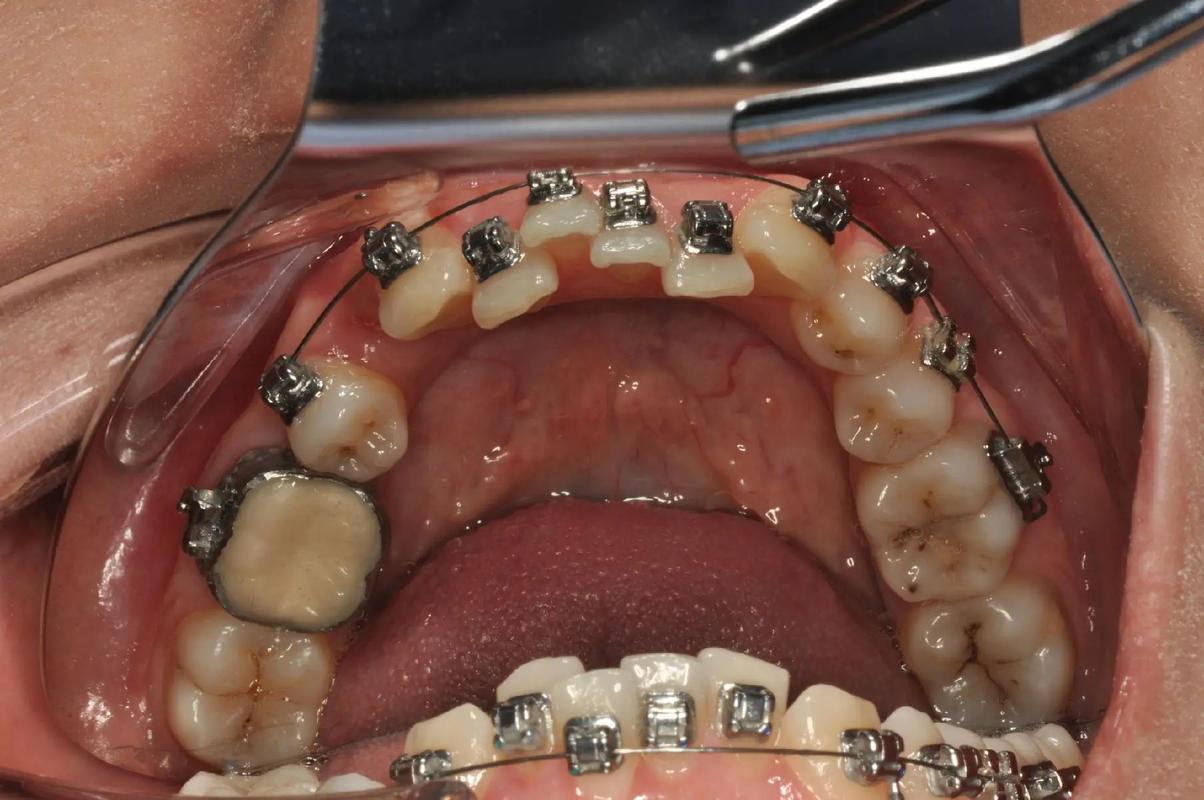

口腔正畸治疗中,带环作为重要的固位装置,主要用于后牙区域的固定,为矫治附件(如颊管、拉钩等)提供稳定基础,不同类型的带环在材料、功能、适应症及制作工艺上存在显著差异,准确区分并合理选择对治疗效果至关重要,以下从多个维度详细解析口腔正畸带环的区分要点。

设计特点:形态为环形,内壁与牙齿邻面贴合,厚度0.1-0.3mm,边缘光滑无锐角,通常无额外附件。

核心功能:单纯提供固位,用于粘接基础矫治附件(如颊管、舌侧管),常见于标准方丝弓矫治器的后牙固定。

制作特点:按标准尺寸批量生产(通常每0.5mm一个型号),分左右侧,内壁为“通用弧度”,临床通过选号试戴调整。

优势:节省取模、制作时间,适合牙齿形态接近标准(如牙冠高度、宽度正常)的病例,尤其适用于儿童或需快速开展治疗的急诊病例。